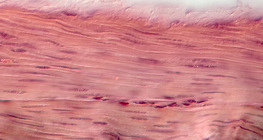

Ampliação de 25x

Ampliação de 1000x

Ampliação de 50x

Ampliação de 100x

Ampliação de 200x

Ampliação de 30x

Ampliação de 15x

Ampliação de 400x

Ampliação de 20x